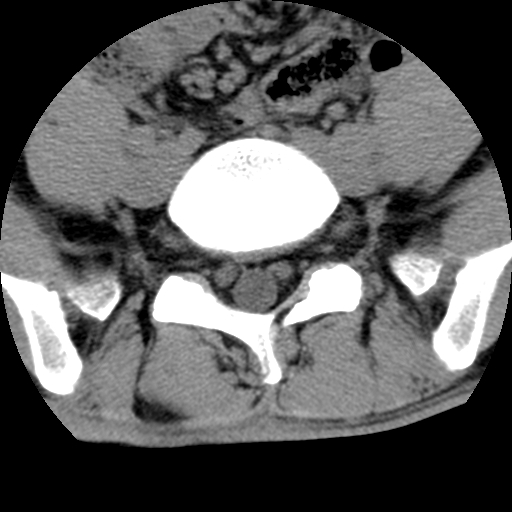

标题: CT16890:男,腰背痛.

男,腰背痛

本人诊断1tb2包虫,请会诊

1)右侧竖脊肌稍低密度肿块伴钙化(性质待定),不排除肿瘤可能;建议行进一步检查。2)腰椎间盘突出。

考神经源性肿瘤可能性,不除外结核,建议增强.椎间盘突出

1.右侧竖脊肌软组织肿块伴团块状钙化,首先考虑血管瘤可能性大;建议行进一步检查;2。腰椎间盘突出。